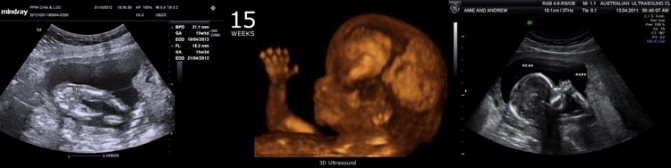

Ниже 15 недель беременности размер плода фото узи:

На 15-й неделе беременности ваш малыш достигает размеров апельсина, яблока или груши, весит примерно 100 граммов и имеет длину около 12 сантиметров. Его ноги начинают расти быстрее, чем руки, а пропорции головы и тела становятся более гармоничными. Ваш ребенок становится все более похожим на человека!

На 15-й неделе беременности что происходит с вашим малышом? Вы можете заметить кровеносные сосуды вашего ребенка сквозь его еще тонкую и полупрозрачную кожу. В это время он начинает покрываться нежными, бархатистыми волосками, известными как лануго, которые помогают ему сохранять тепло в материнской утробе. Формирование черепа продолжается, а остальные кости начинают укрепляться. На 15-й неделе беременности ваш плод уже освоил такие процессы, как дыхание, сосание и глотание, и даже может делать различные гримасы, тренируя свои лицевые мышцы. Что касается ощущений в животе на 15-й неделе беременности, возможно, ваш малыш уже начал икать в вашем животе.

На 15-й неделе беременности врачи отмечают значительные изменения в развитии плода. В этот период размер эмбриона достигает около 10 см, а вес составляет примерно 70 граммов. Врачи подчеркивают, что формируются основные органы и системы, что способствует дальнейшему развитию. Сердце уже активно перекачивает кровь, а в организме плода начинают функционировать почки, которые отвечают за выведение жидкости.

| 15 | Размер: Примерно 10-11 см от макушки до крестца, вес около 70-80 грамм. Органы: Продолжается активное развитие внутренних органов. Сердце перекачивает около 28 литров крови в день. Движения: Плод становится более активным, совершает разнообразные движения, которые мама пока не чувствует. Кожа: Кожа очень тонкая, просвечивают кровеносные сосуды. Начинает формироваться лануго (тонкие волоски). Лицо: Черты лица становятся более выраженными, глаза расположены ближе друг к другу. | Матка: Продолжает расти, ее верхний край может быть уже ощутим на 7-10 см ниже пупка. Симптомы: Утренняя тошнота обычно проходит. Может появиться изжога, запоры. Грудь: Грудь продолжает увеличиваться, могут быть видны вены. Энергия: Уровень энергии может повыситься. Кожа: Возможно появление пигментных пятен (хлоазма) на лице и темной линии (линия нигра) на животе. |